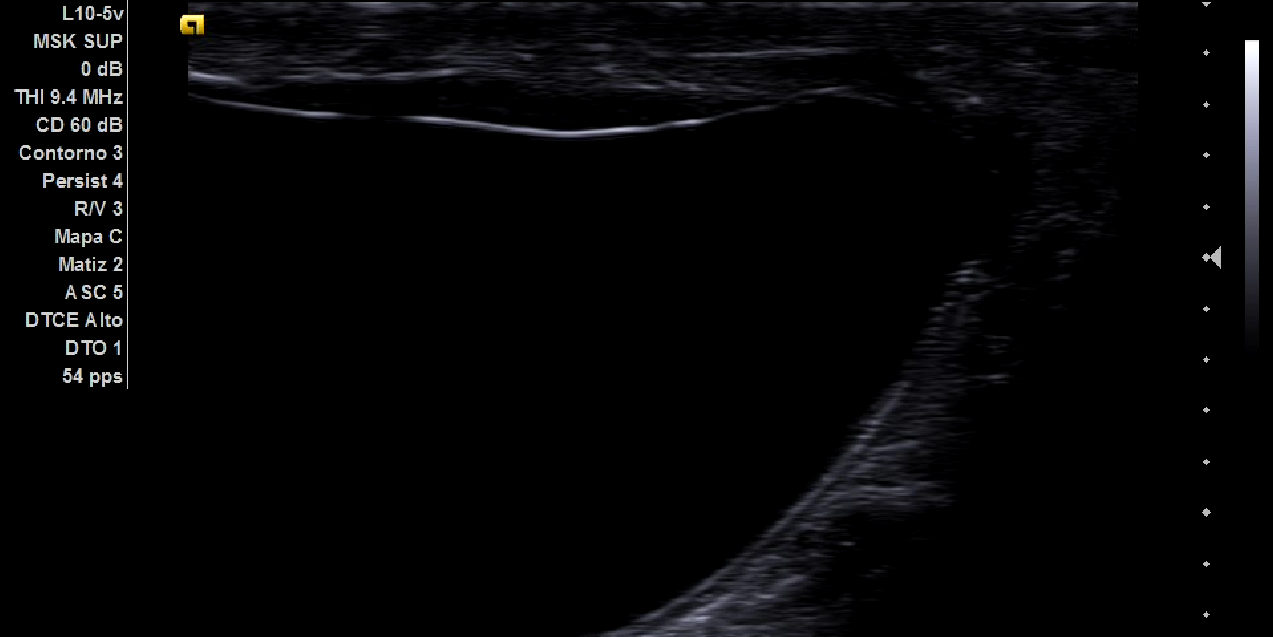

Al realizar la ecografía se aprecia masa heterogénea, móvil, con cordón espermático en la superficie (imagen 1), destacando que en el escroto había abundante contenido hipoecoico compatible con hidrocele. Todos ellos hallazgos compatibles con hernia inguinal de grandes dimensiones.

La hernia inguinal es un diagnóstico que puede realizarse sin apenas uso de pruebas complementarias, tan solo con una adecuada y sistemática exploración física. Sin embargo, con la llegada de la ecografía a los centros de salud, disponemos de una herramienta fundamental para realizar un primer abordaje de una masa abdominal. En el caso de sospechar una hernia inguinal en un hombre de debe comenzar por situar el transductor en posición transversal sobre el testículo, y se debe buscar el cordón espermático (en la superficie de la imagen 1), siguiéndolo proximalmente al anillo superficial hasta su desaparición en el anillo profundo. Se debe evaluar toda la extensión de la hernia, rastreando hasta su origen. Tener en cuenta que si se localiza lateralmente a la arteria epigástrica inferior es una hernia indirecta; de lo contrario, es directa. También es útil evaluar el Doppler para cerciorarnos de que el asa puede ser viable.